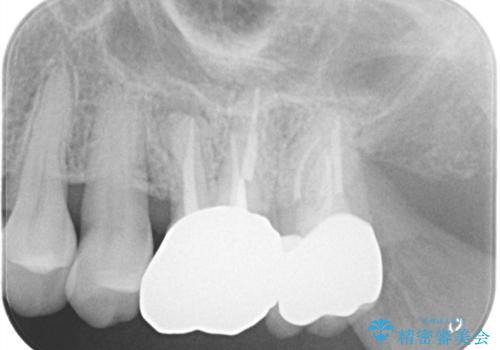

左上7番の歯は、歯髄検査にて反応を示し、歯周ポケットはありませんでした。

親知らず抜歯を行い、痛みの変化や歯根吸収の有無を確認したのち、抜髄処置を行っています。

症状改善し、遠心の骨の回復も認めます。